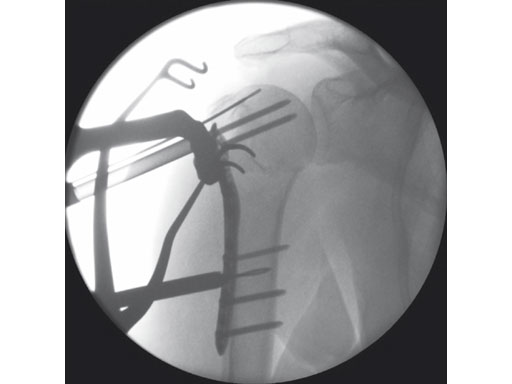

The 3.5 mm LCP percutaneous aiming system for PHILOS offers the possibility to insert the PHILOS plate through the transdeltoid approach and to insert the shaft screws percutaneously enabling a less-invasive application of PHILOS.

The system consists of a sleeve system and an aiming arm. It is used analogously to the existing PHILOS aiming instruments and other aiming systems. The aiming arm is radiolucent to allow control under image intensifier. Locking as well as cortex screws can be used through the device. Compression achieved by cortex screws in the shaft may lead to plate tension. The device has to be locked to the plate at both ends to ensure the plate-device alignment.

A safe zone is defined to protect the axillary nerve (screw holes near the axillary nerve are not accessible through the device). Therefore, the elongated plate hole is not accessible through the aiming arm due to the protected nerve zone. However, by abduction of the arm after fixation, these screw holes become accessible.

Overall, the 3.5 mm LCP percutaneous aiming system facilitates plate insertion as well as positioning and adjustment.